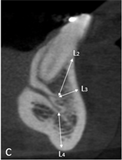

The following measurements were performed: longest width of the genial canal (W) or (D); longest length of the genial canal in relation to the alveolar bone crest (L) or (L1); (D1) or (L2), which was performed between the uppermost portion of the genial plexus and the alveolar bone crest (for dentate patients the reference was the buccal bone crest); shortest distance from the genial plexus to the buccal cortical bone (D2) or (L3), which was performed between the most vestibular portion of the genial plexus and the buccal cortical bone; (D3) or (L4), which was performed between the lowest portion of the genial plexus and the cortical part of the mandible base (Figures 1(B)-(D)).

Figure 3(A) is the initial parasagittal tomographic image of an edentulous patient. Figure 3(B) is the parasagittal tomographic image in which the largest length of the genital canal (L or L1) was measured. Figure 3(C) is the parasagittal tomographic image in which the largest diameter of the genital plexus (W or D) was measured. Figure 3(D) is the tomographic image in which the lowest distance from the genital plexus to the alveolar bone crest (D1 or L2) was measured; in this case, as the foramen, this surface was zero; shorter distance from the plexus to the cortical buccal (D2 or L3); and shorter distance from the plexus to the base of the mandible (D3 or L4).

Figure 1. Tomographic images, diameters and distances of the canal and plexus. (A) Parasagittal tomographic image; (B) Canal diameter; (C) Distance from the genial plexus to the cortical bone; (D) Initial parasagittal tomographic image, central incisor tooth. Source: Own Authorship. Caption: Parasagittal tomographic image measuring the length (A) canal diameter (B) and distances as follows: (L1) of the genial canal; (L2) distance from the genial plexus to the alveolar bone crest, (L3) distance from the genial plexus to the buccal cortical bone and the base of the mandible (L4) (C), initial parasagittal tomographic image (D). Figure 1 (A) Parasagittal section of the CBCT used to perform measurements. (B) Longest width of the genial canal (W). (C) longest length of the genial canal (L). (D) Shortest distance from the genial plexus to the alveolar bone crest (D1); shortest distance from the genial plexus to the buccal cortical bone (D2); shortest distance from the genial canal relative to the base of the mandible (D3).